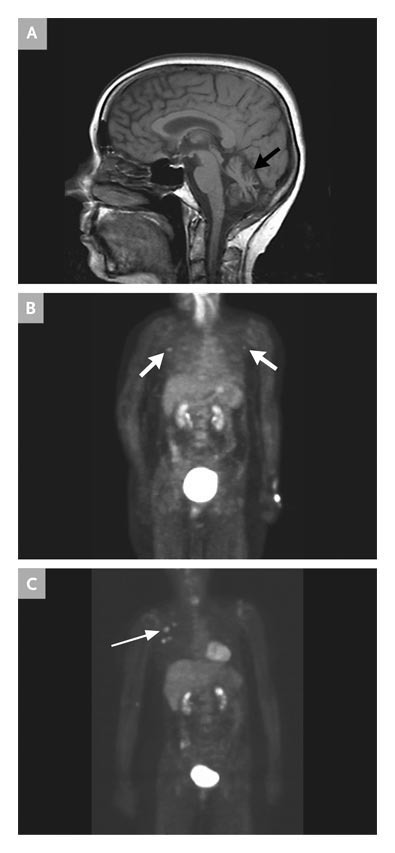

A sagittal T1-weighted MRI scan shows shrinkage of the cerebellar vermis (arrow, top panel) and a PET scan shows small areas of uptake in the axillae (arrows, middle and lower panels)(left image). Excisional biopsy of the right axillary node shows diffuse involvement with gross cystic disease fluid protein-15 positive tumor cells (panel C), a finding see in breast, salivary gland and adrenal tumors.